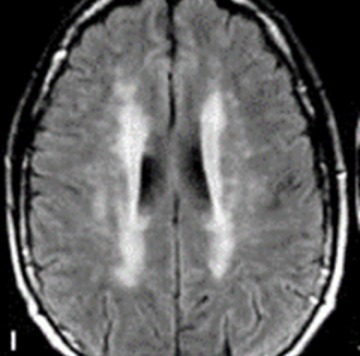

Синдром сопровождается типичными для ЗСОНМ поражениями головного мозга на МРТ: в аксиальной плоскости наблюдается двустороннее глубокое поражение белого вещества, а в сагиттальной плоскости видны острые поражения в периэпендимальных отделах головного мозга.

Церебральный синдром в большинстве случаев ассоциируется с крупными, сливными подкорковыми очагами или с глубоким поражением белого вещества. Он может включать в себя следующие проявления:

МРТ в аксиальной плоскости при ЗСОНМ показывает двустороннее сливное глубокое поражение белого вещества5